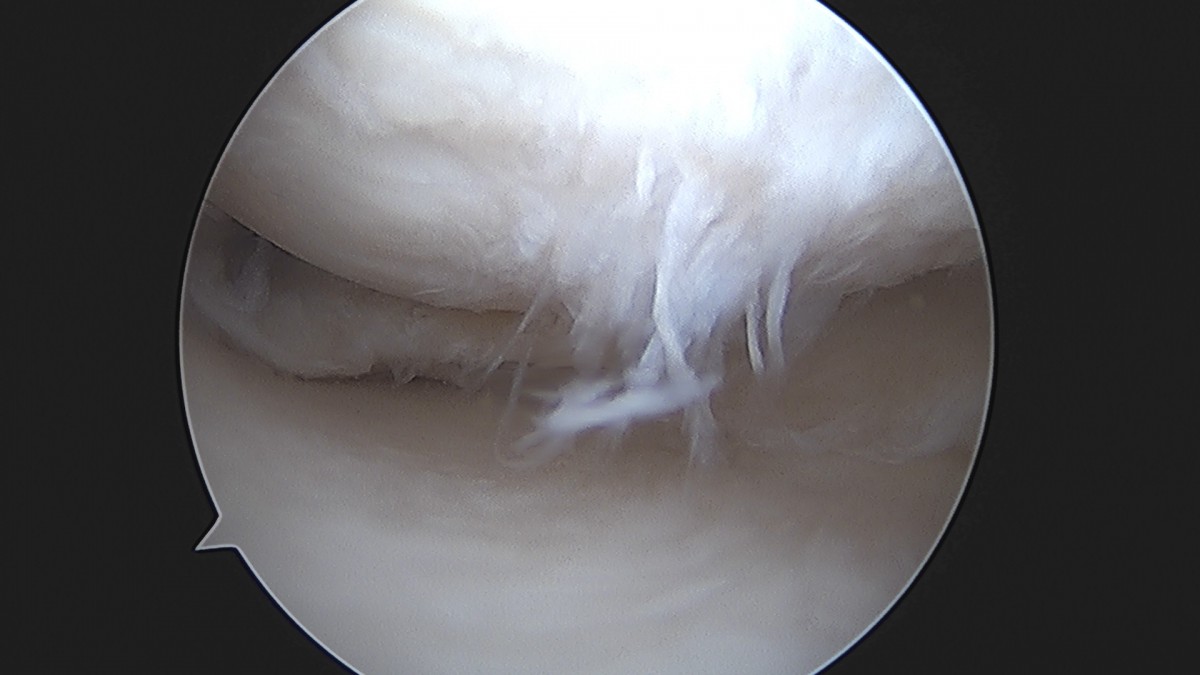

이재상원장님 무릎 반월상 연골판 절제술 장영O 환자

작성자 최고관리자 댓글 0건 조회 369회 작성일 25-09-16 16:02